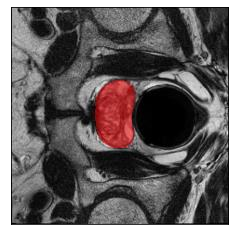

Machine learning models are typically deployed in a test setting that differs from the training setting, potentially leading to decreased model performance because of domain shift. If we could estimate the performance that a pre-trained model would achieve on data from a specific deployment setting, for example a certain clinic, we could judge whether the model could safely be deployed or if its performance degrades unacceptably on the specific data. Existing approaches estimate this based on the confidence of predictions made on unlabeled test data from the deployment's domain. We find existing methods struggle with data that present class imbalance, because the methods used to calibrate confidence do not account for bias induced by class imbalance, consequently failing to estimate class-wise accuracy. Here, we introduce class-wise calibration within the framework of performance estimation for imbalanced datasets. Specifically, we derive class-specific modifications of state-of-the-art confidence-based model evaluation methods including temperature scaling (TS), difference of confidences (DoC), and average thresholded confidence (ATC). We also extend the methods to estimate Dice similarity coefficient (DSC) in image segmentation. We conduct experiments on four tasks and find the proposed modifications consistently improve the estimation accuracy for imbalanced datasets. Our methods improve accuracy estimation by 18\% in classification under natural domain shifts, and double the estimation accuracy on segmentation tasks, when compared with prior methods.